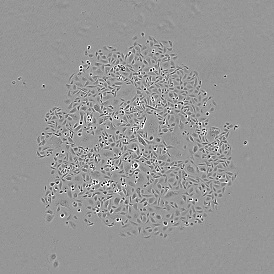

The IF Cardio Cell Culture App provides cell segmentation, detection of cardiomyocytes (based on appropriate staining, e.g., Troponin Red), fibroblasts within cultured cardio cells, plus one additional marker. The App outputs parameters such as the number of cardiomyocytes, fibroblasts, and marker-positive cardiomyocytes and fibroblasts.

Image: Courtesy of Agatha Ribeiro da Silva, Prof. Jose E. Krieger (Heart Institute, University Sao Paulo)